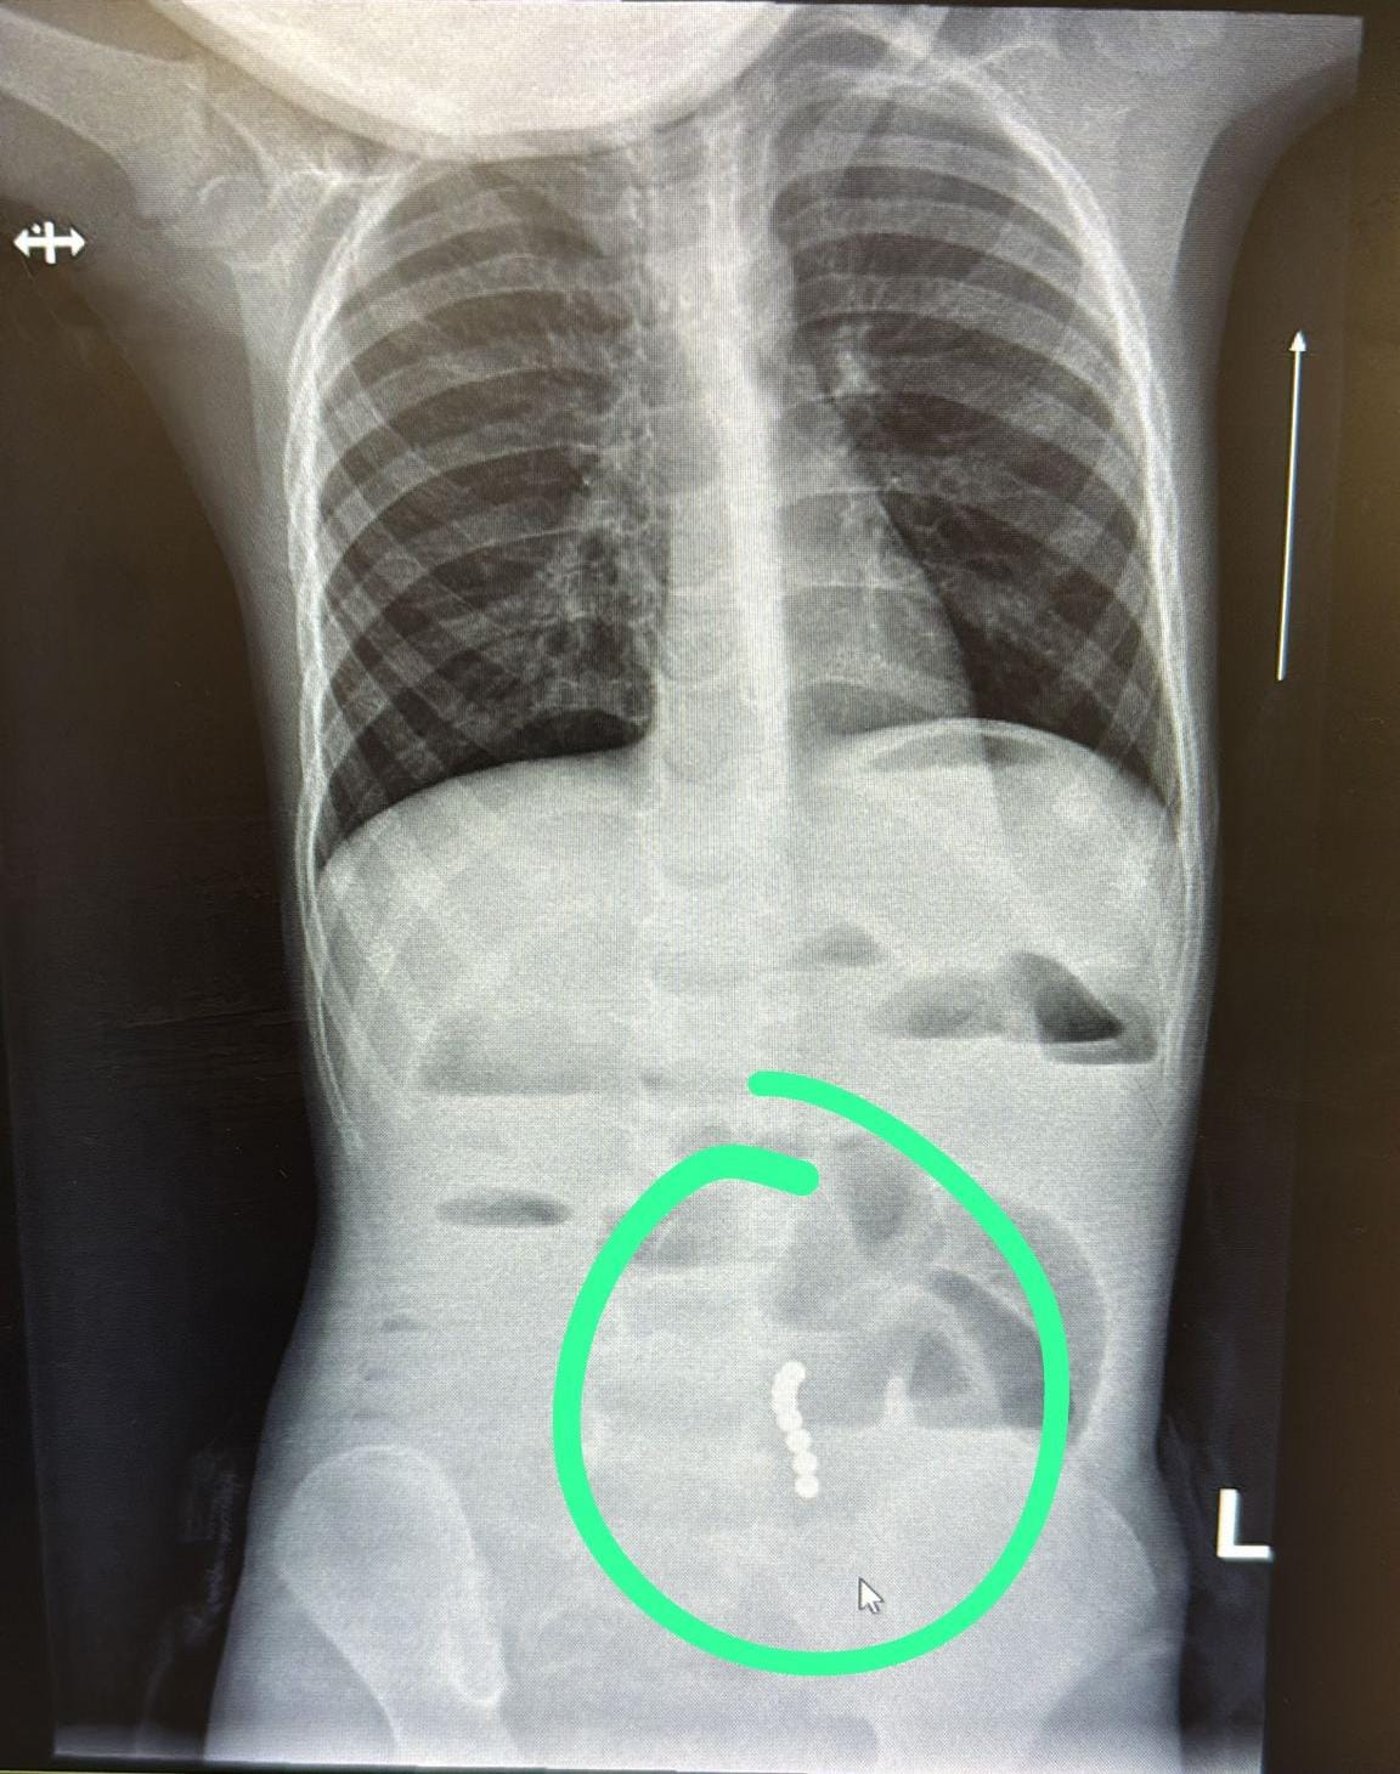

ד”ר ליאת יניב, רופאה בכירה במחלקת ילדים במרכז הרפואי בני ציון, זיהתה ממצא שעורר חשד לבעיה משמעותית במערכת העיכול. בצילום הדמיה שבוצע בדחיפות, הודגמו מגנטים במעי הדק עם עדות לחסימת מעי.

בהתייעצות עם ד"ר ראוף נאסר, מומחה גסטרו ילדים, הפעוט הופנה להמשך טיפול כירורגי ונותח באופן דחוף ע"י ד”ר דניאל דובין, סגן מנהלת מחלקת כירורגיית ילדים במרכז הרפואי בני ציון ו ד"ר יאיר בן שמואל, רופא בכיר בכירורגיית ילדים, כאשר ד"ר אבו ראס עומר היה הרופא המרדים הבכיר. בניתוח הוצאו שמונה כדורי מגנט מהמעי הדק.